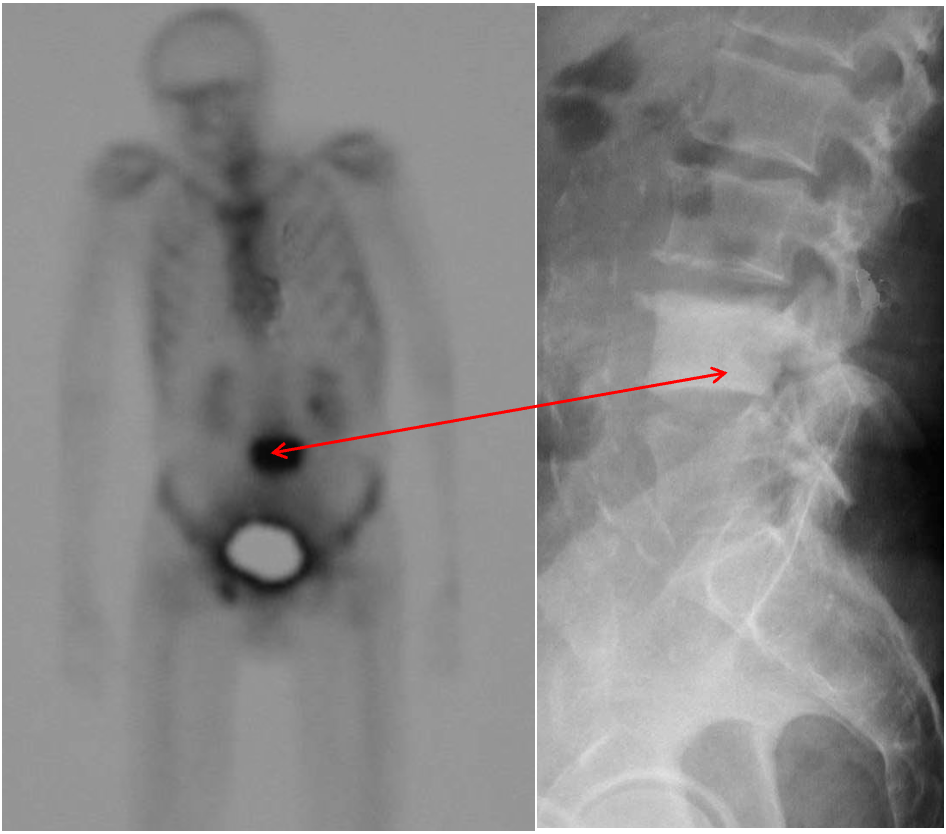

The nuclear bone scan

shows increased activity at site. Prostate malignancy often metastasizes to the skeleton and is usually sclerotic (dense) .